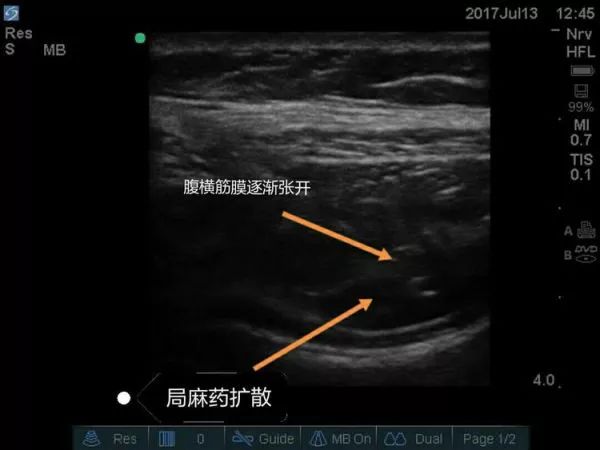

超声引导下腹横平面TAP阻滞要点

①适应证: 剖腹手术、阑尾切除术、腹腔镜手术、剖宫产术后镇痛。

②探头位置: 横向放置在肋缘和髂棘之间腋前线处的腹壁。

③目标: 局麻药在腹横肌和腹内斜肌之间扩散。

④局麻药: 每侧0.25%罗哌卡因20-30ml。

超声下孕妇的腹横筋膜图像

超声引导下腹横筋膜阻滞技术优点:

①为普外科手术如疝气提供麻醉。

②为伴有脊柱病变的剖宫产患者提供麻醉。

③妇科手术的术后镇痛。